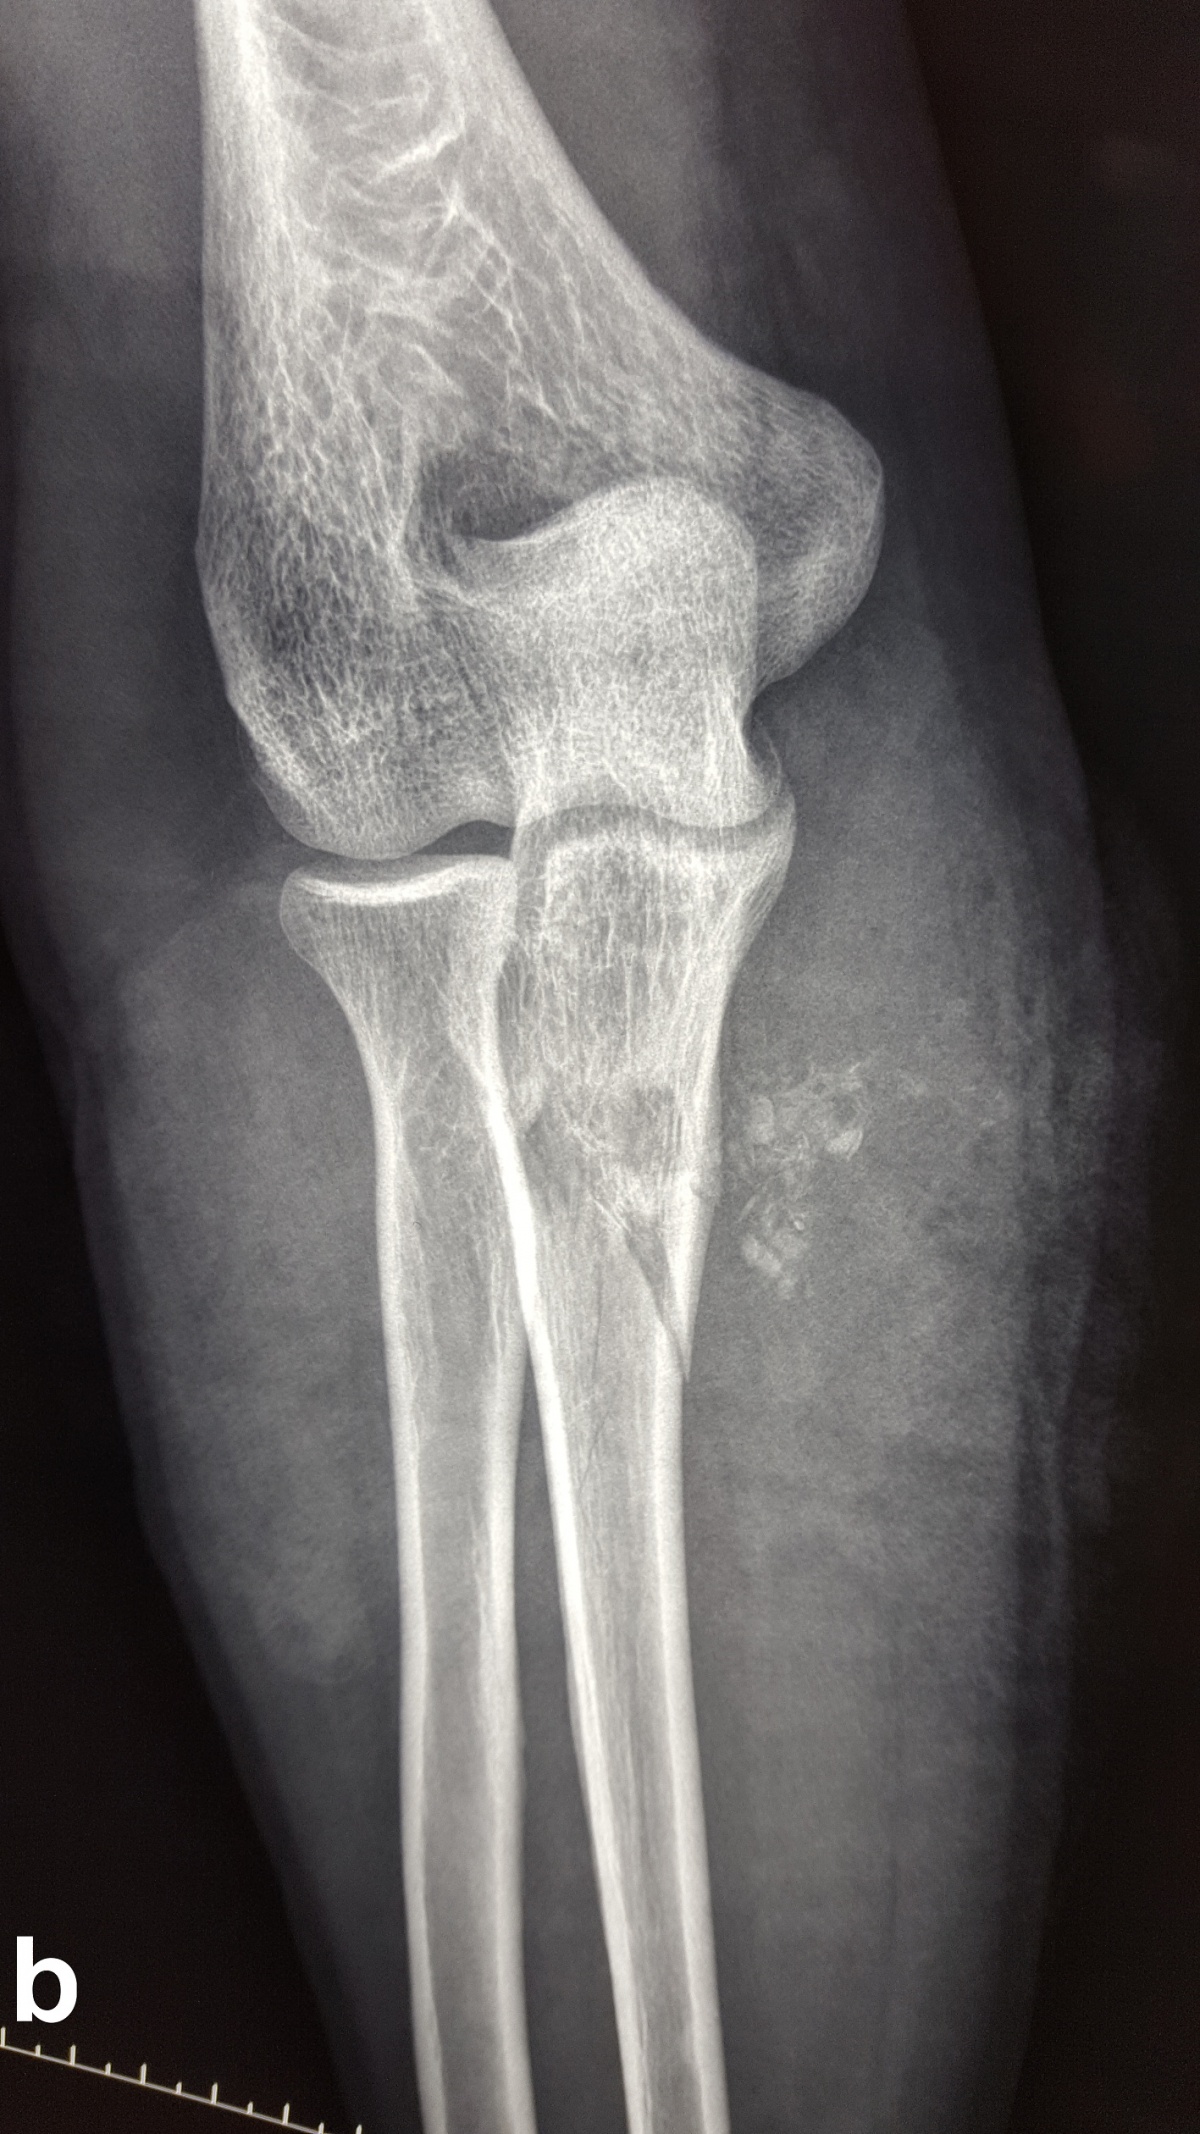

Beim Auftreffen des Projektils im Rahmen von Niedrigenergieverletzungen auf Knochengewebe entsteht meist eine typische, einfache Fraktur (Abbildung 2). Hochenergieverletzungen des Knochens münden in eine multifragmentäre Situation, bei der ein Großteil der Projektilenergie an den Knochen abgegeben wird. Insbesondere lange Röhrenknochen können, da sie wie eine starre, spröde flüssigkeitsgefüllte Röhre agieren, durch Projektile mit hoher Energie explosionsartig zerstört werden (Abbildung. 3).

Nach Steckschussverletzungen, insbesondere durch Niedrigenergiegeschosse, stellt sich Frage, ob das Projektil entfernt werden muss (Abbildung 5). Ist das Projektil nicht zu tasten und liegt es im Weichteilgewebe außerhalb von Gelenken, kann es durchaus belassen werden [1]. Bei Projektilen in Gelenken ist die Entfernung anzustreben, da durch sekundäre Schäden bei Bewegung durch Abrieb der Gelenkfläche auftreten können [1]. Zudem ist eine Bleiintoxikation durch in den Gelenken verbliebene Projektile möglich [51, 52].